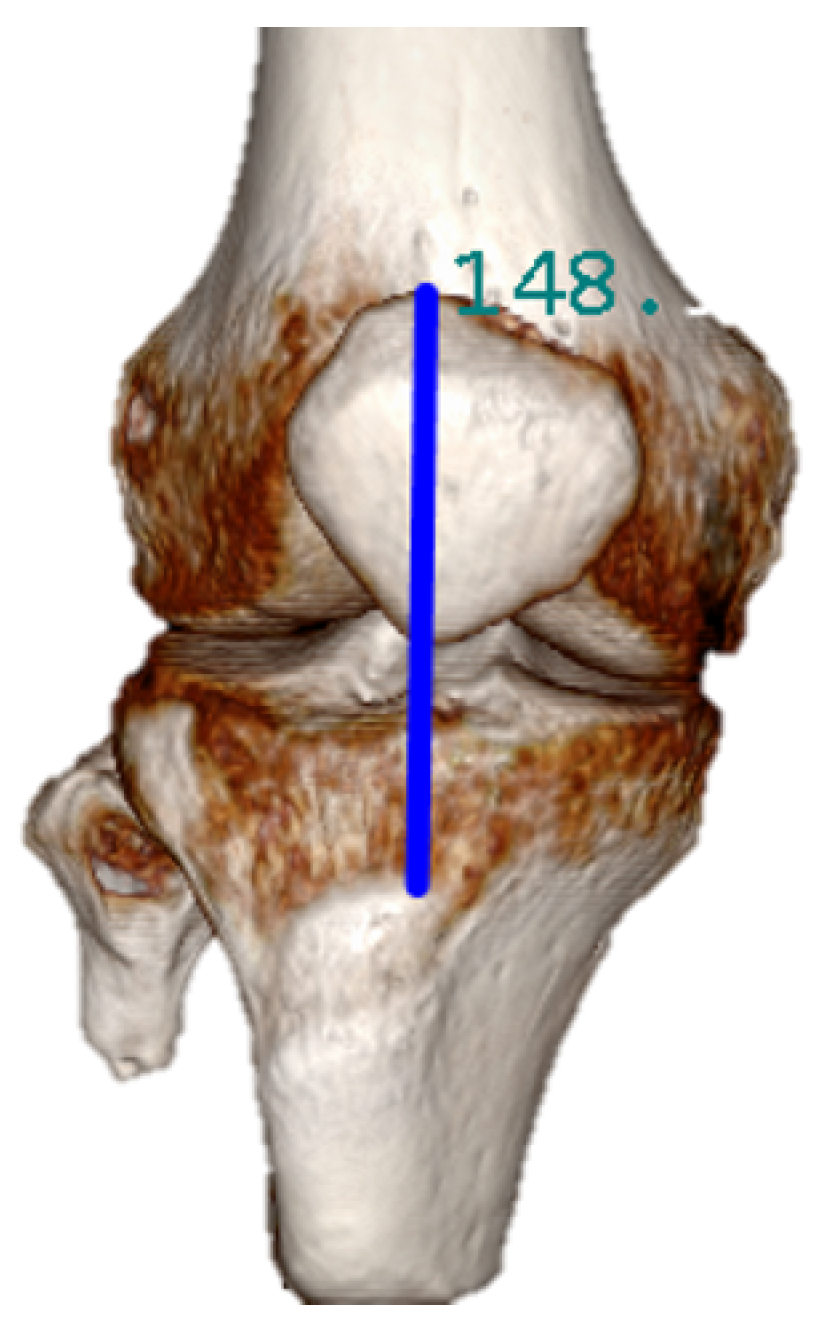

2.3. Croi Location